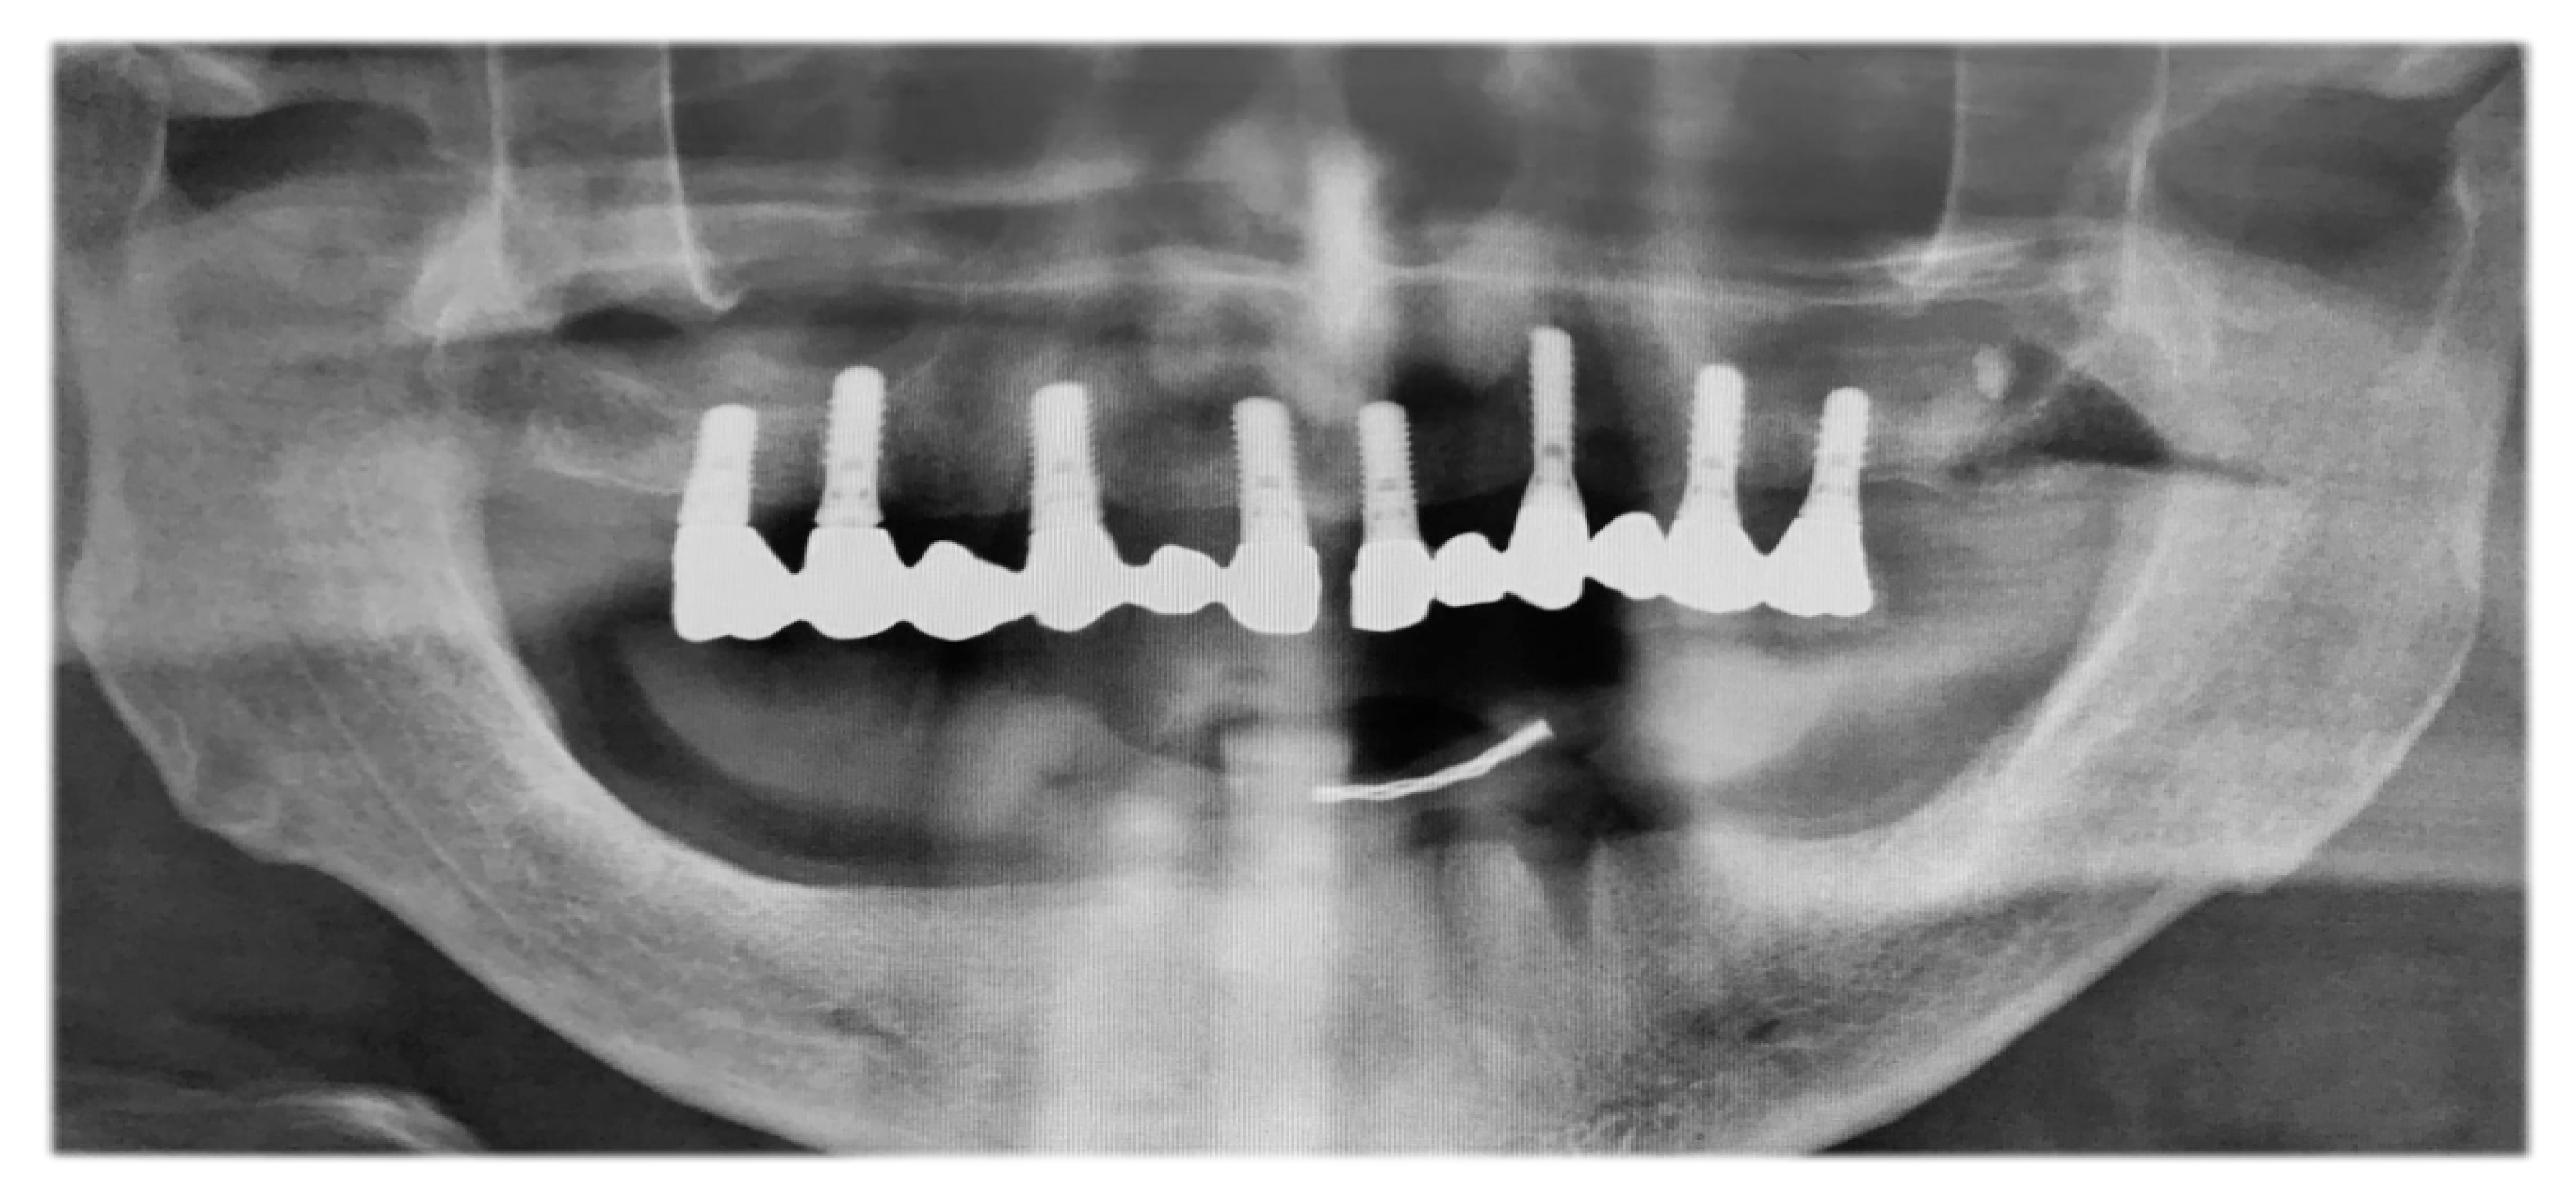

3.2. Preoperative Oral Situation

3.3. Preoperative Protocol

3.4. Preoperative Digital Planning